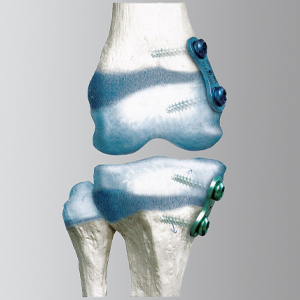

Ein weiterer Schwerpunkt der kinderorthopädischen Versorgung sind Achsdeformitäten (X- oder O-Beine). Hier gilt es zunächst zu entscheiden, ob die Deformität tatsächlich im knöchernen Bereich vorliegt. Hierzu werden so genannte Ganzbeinaufnahmen angefertigt. Wenn hierbei nachweisbar ist, dass die Belastungsachse außerhalb der Mitte des Kniegelenks fällt, sollte eine operative Korrektur der Beinachse in Erwägung gezogen werden. Bei einer ungleichmäßigen Belastung der Kniegelenke kommt es ansonsten im Laufe des Lebens zu einem Mehrverschleiß des überbelasteten Anteils und damit zu Überlastungsschäden an Knorpel und Menisken. Während beim Erwachsenen die Begradigung eines Achsfehlers relativ aufwändig ist, kann bei Kindern im Wachstum durch eine einfache Überklammerung der Wachstumsfugen auf einer Seite ein entsprechendes Korrekturwachstum erzeugt werden, so dass sich die Beine begradigen. Wir setzen hierzu spezielle 8-förmige Plättchen (so genannter Eightplates) ein, die nach Erreichen der richtigen Achse wieder entfernt werden können. Das gleiche System kann auch zur Korrektur unterschiedlich langer Beine angewendet werden.